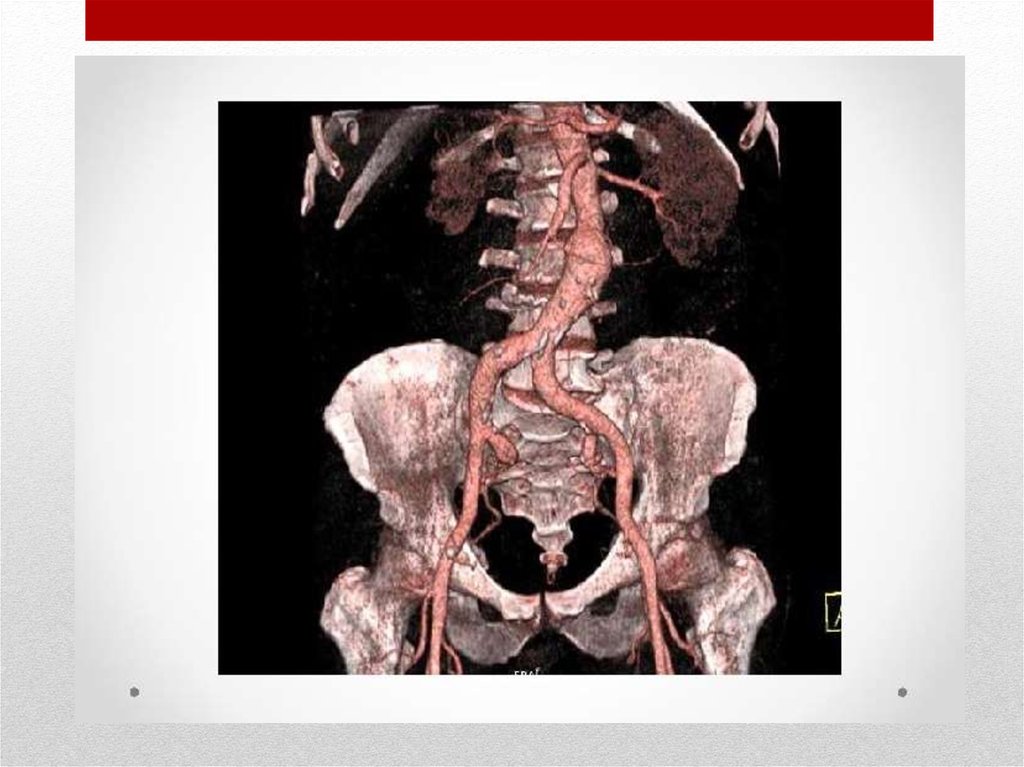

Аневризма брюшной

аорты